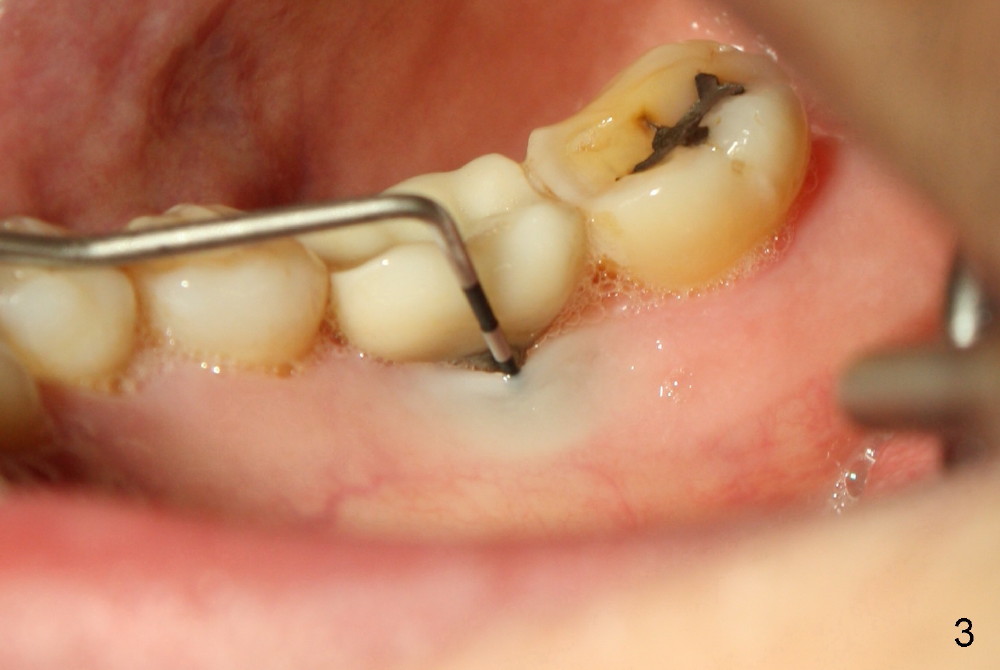

Thirteen months post bone graft via buccal approach, the patient has remained asymptomatic. There is no sign of infection buccally (Fig.1), but the lingual gingiva is erythematous (Fig.2 arrowheads) with deep pocket (Fig.3). Since the patient will be out of country for 7 months, exploration is going to be done immediately. Preop PA reveals mesial bone loss (Fig.4 M).